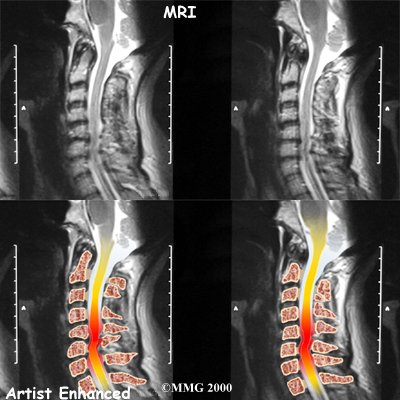

MRI

The magnetic resonance imaging (MRI) scan uses magnetic waves to create pictures of the cervical spine in slices. The MRI scan shows the cervical spine bones, as well as the soft tissue structures such as the discs, joints, and nerves.

MRI scans are painless and don't require needles or dye. The MRI scan has become the most common test to look at the cervical spine after X-rays have been taken.